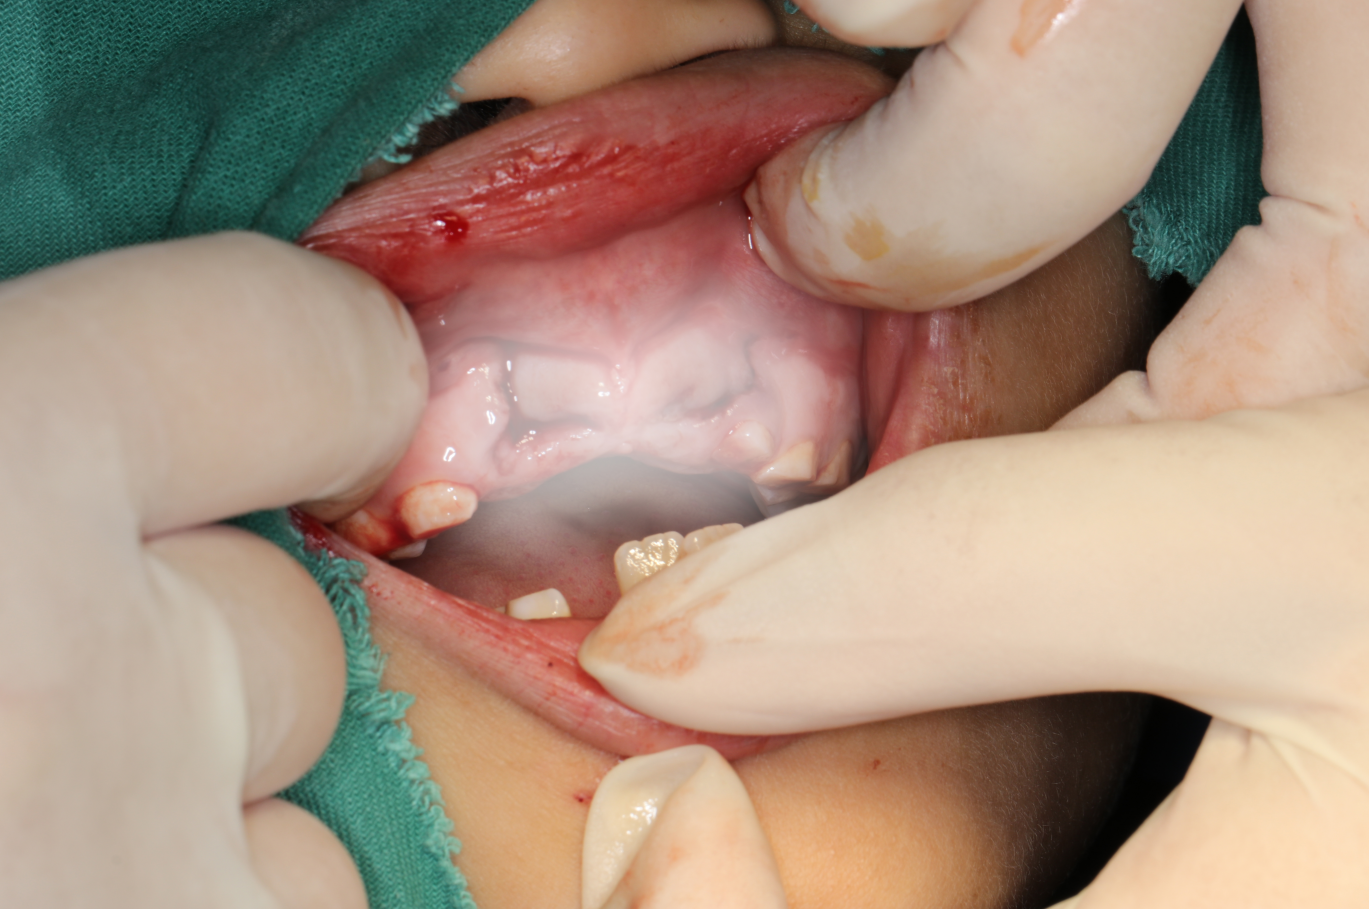

经过口外检查发现患儿的面下1/3可见部分擦伤,少量出血,上唇肿胀,开口型及开口度没有明显异常,而且11、21号脱落的恒牙保存在冰牛奶中,根尖呈喇叭口未闭合,根部可见牙周膜软组织,牙体组织保存良好。

在治疗过程中,我先为患儿先进行牙槽骨复位+11、21号恒牙再植+术后牙周钢丝+树脂纤维带固定,同时对上颌牙列进行颌垫保护。

因为患儿52、62号牙均无法参与固定,我们选择用树脂纤维带进行第二重固定,术后配合数字化口扫收集患儿口内信息,制作上颌牙列的颌垫作为第三重固定。